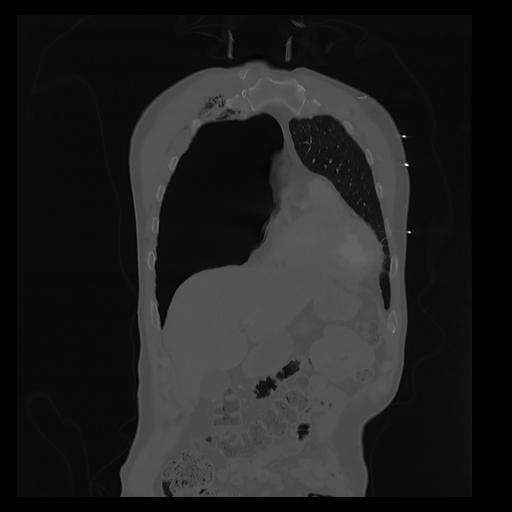

32 PULMON,CE,Coronal,3.000,PULMON,Coronal,